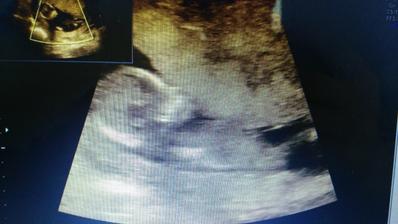

12.6.2017 Screening v 1 trimestru. JSI KRÁSNÁ ZDRAVÁ HOLČIČKA!!! TP podle MS i UZ 18.12.2017

22.6.2017 kontrolní ultrazvuk. Jsi v pořádku, mávalas mi ručičkama a hopsala 🙂